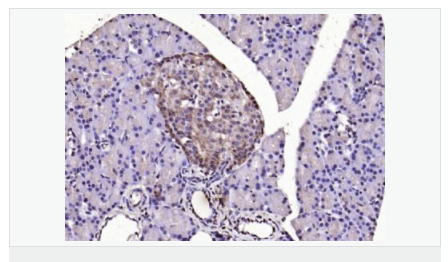

| 英文名稱(chēng) | LSM3 |

| 中文名稱(chēng) | LSM3蛋白抗體 |

| 別 名 | lsm3; LSM3 homolog; LSM3 protein; LSM3_HUMAN; MDS017; SMX4; U6 small nuclear RNA associated (S. cerevisiae); U6 snRNA associated Sm like protein LSm3; U6 snRNA-associated Sm-like protein LSm3; USS2; YLR438C. |

| 研究領(lǐng)域 | 細胞生物 結合蛋白 表觀(guān)遺傳學(xué) |

| 產(chǎn)品應用 | WB=1:500-2000 ELISA=1:5000-10000 IHC-P=1:100-500 IHC-F=1:100-500 ICC=1:100-500 IF=1:100-500 (石蠟切片需做抗原修復) not yet tested in other applications. optimal dilutions/concentrations should be determined by the end user. |

| 細胞定位 | 細胞核 |

| 產(chǎn)品介紹 | Sm-like proteins were identified in a variety of organisms based on sequence homology with the Sm protein family (see SNRPD2; MIM 601061). Sm-like proteins contain the Sm sequence motif, which consists of 2 regions separated by a linker of variable length that folds as a loop. The Sm-like proteins are thought to form a stable heteromer present in tri-snRNP particles, which are important for pre-mRNA splicing.[supplied by OMIM, Apr 2004] Function: Binds specifically to the 3'-terminal U-tract of U6 snRNA. Subcellular Location: Nucleus. Similarity: Belongs to the snRNP Sm proteins family. SWISS: P62310 Gene ID: 27258 Database links: Entrez Gene: 27258 Human Omim: 607283 Human SwissProt: P62310 Human Unigene: 111632 Human Important Note: This product as supplied is intended for research use only, not for use in human, therapeutic or diagnostic applications. |